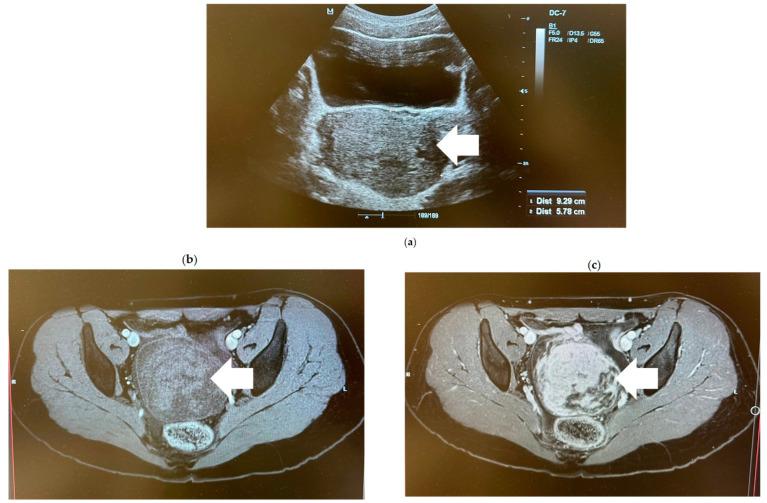

An ovarian Sertoli-Leydig cell tumor is a rare type of sex cord-stromal tumor of the ovary. Typically, it presents as abdominal pain or androgenic manifestations in women in the second to third decade of life. While cases of ovarian Sertoli-Leydig cell tumor associated with increased levels of alpha-fetoprotein are rare, they are reported to be the most common alpha-fetoprotein-producing ovarian non-germ cell tumor. We report the case of a 16-year-old patient, who presented with complaints of amenorrhea that had lasted for one year. Transabdominal ultrasound revealed the presence of a tumor in the right ovary, measuring 9.3 × 5.8 cm in size. The laboratory investigation showed an increased level of alpha-fetoprotein. The patient underwent laparoscopic right salpingo-oophorectomy. Histopathological examination confirmed the presence of a moderately differentiated (G2) Sertoli-Leydig cell tumor in the right ovary. For reproductive-age patients with disease confined to the ovary, fertility-sparing surgery is recommended. According to the current recommendations, the administration of adjuvant chemotherapy is indicated in cases of the presence of heterologous elements, poorly differentiated tumors, or FIGO stages IB-IV. As there were no high-risk factors and no residual disease in this case, there were no indications for further treatment with adjuvant chemotherapy. A recent follow-up visit showed that the patient is in complete remission. This report presents a detailed description of the findings, differential diagnosis, clinical course, chosen treatment, and prognosis. Also, a comprehensive literature review of ovarian Sertoli-Leydig cell tumors, focusing on their clinical presentation, laboratory findings, macroscopic and histopathological features, genetics, clinical management, prognostic factors and follow-up, is provided.

卵巢 Sertoli-Leydig 细胞瘤是一种罕见的卵巢性索-间质肿瘤。它通常表现为第二至第三十年纪女性的腹痛或雄激素表现。虽然伴有甲胎蛋白水平升高的卵巢 Sertoli-Leydig 细胞瘤病例罕见,但它们被认为是最常见的产生甲胎蛋白的卵巢非生殖细胞瘤。我们报告了 1 例 16 岁患者,因闭经 1 年就诊。经腹超声显示右侧卵巢有一个肿瘤,大小为 9.3×5.8cm。实验室检查显示甲胎蛋白水平升高。患者接受了腹腔镜右侧输卵管卵巢切除术。组织病理学检查证实右侧卵巢存在中分化(G2)Sertoli-Leydig 细胞瘤。对于局限于卵巢的疾病的生育期患者,建议进行保留生育功能的手术。根据目前的建议,对于存在异源性成分、低分化肿瘤或 FIGO 分期 IB-IV 的病例,应给予辅助化疗。由于该病例无高危因素且无残留疾病,因此无需进一步接受辅助化疗。最近的随访显示患者完全缓解。本报告详细描述了发现、鉴别诊断、临床过程、选择的治疗方法和预后。还提供了对卵巢 Sertoli-Leydig 细胞瘤的全面文献复习,重点介绍了其临床表现、实验室发现、大体和组织病理学特征、遗传学、临床管理、预后因素和随访。